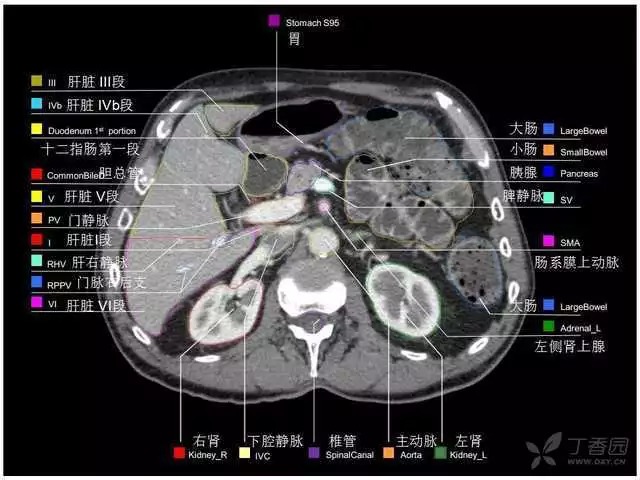

腹部肝脏高清CT断层的图谱

全腹部高清CT图谱,淋巴结彩色图谱,血管解剖图谱大汇总!

超声肝脏分叶及分段

肝脏分段和基本解剖学标志